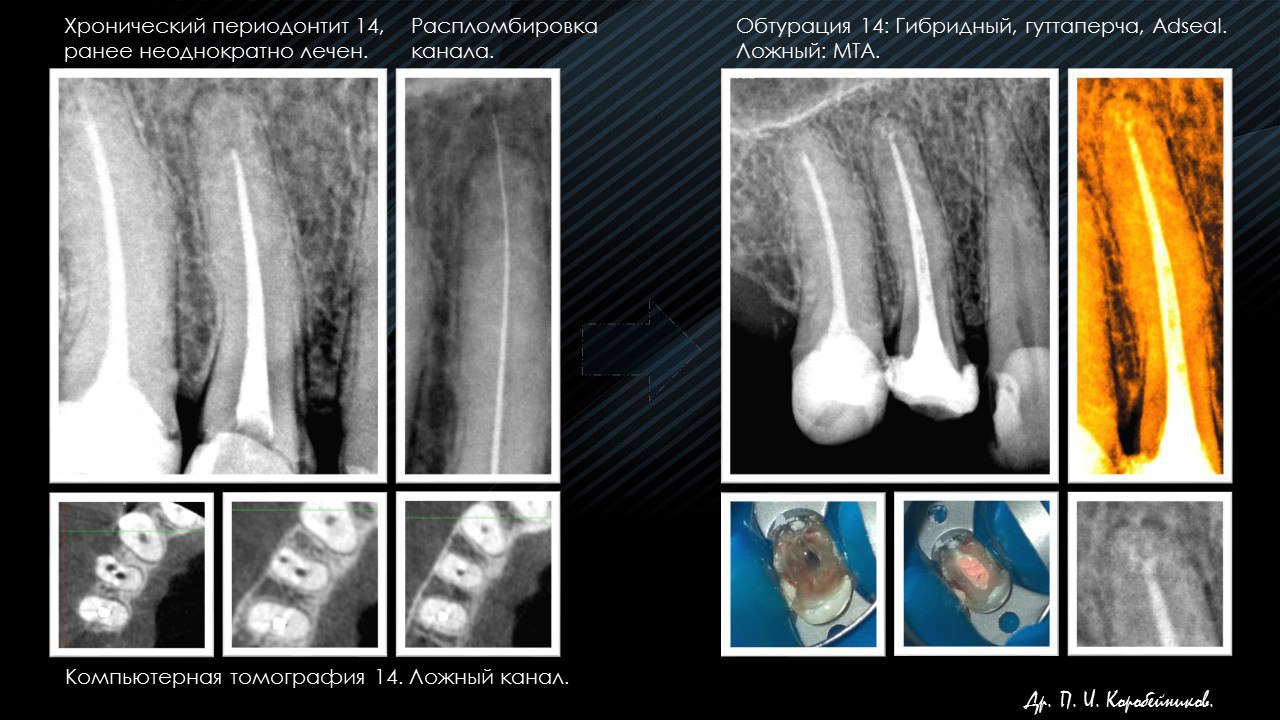

Стоматолог- эндодонт, стоматолог- терапевт, стоматолог- ортопед, стоматолог- хирург.

Работа с микроскопом, консультации и лечение пациентов, эндодонтия, терапия, ортопедия, хирургия(в небольшом объеме).